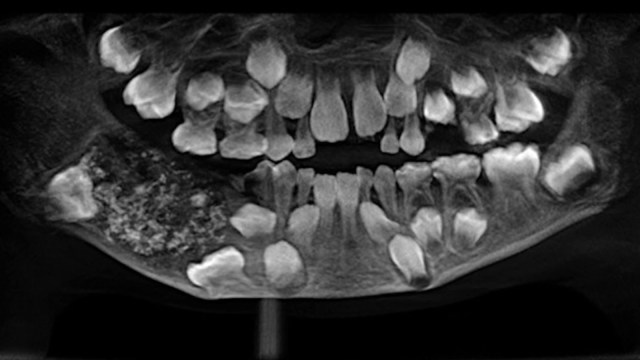

When doctors scanned and x-rayed his mouth, they found a sac embedded in his lower jaw filled with “abnormal teeth,” Dr. Prathiba Ramani, the head of Oral and Maxillofacial Pathology at Saveetha Dental College and Hospital, told CNN.

“There were a total of 526 teeth ranging from 0.1 millimeters (.004 inches) to 15 millimeters (0.6 inches). Even the smallest piece had a crown, root and enamel coat indicating it was a tooth,” she said.